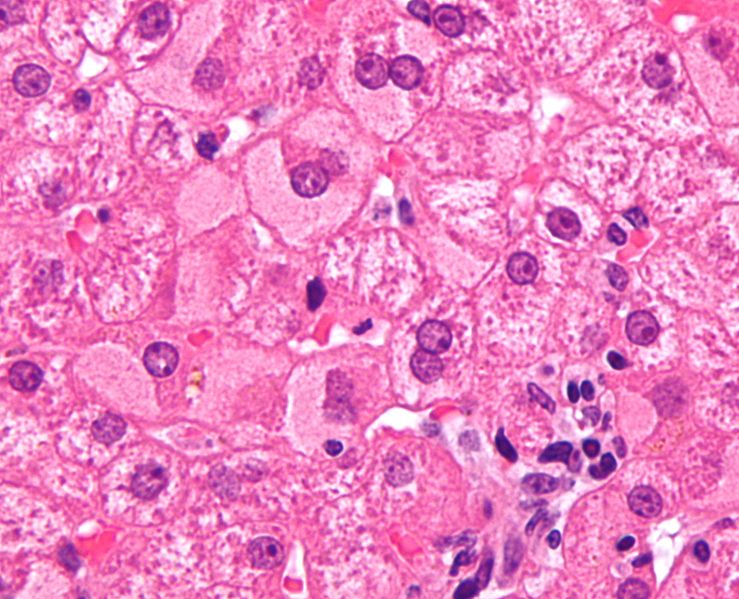

foto http://en.wikipedia.org/wiki/Viral_hepatitis